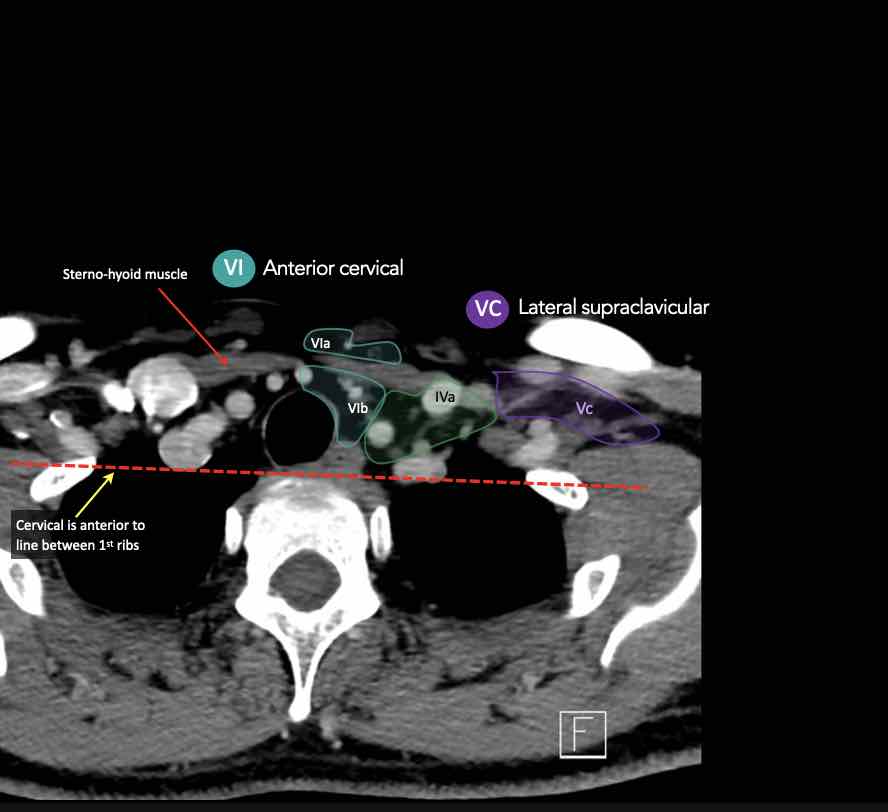

VI – Cổ trước

Tầng này chứa các hạch tĩnh mạch cảnh trước nông (tầng VIa) và các hạch sâu hơn bao gồm hạch trước thanh quản, trước khí quản, cạnh khí quản và hạch thần kinh thanh quản quặt ngược (tầng VIb).

Tầng Vc – Hố thượng đòn

Tầng này chứa các hạch thượng đòn bên nằm trong phần tiếp nối của các hạch tam giác cổ sau (tầng Va và Vb) từ các mạch máu cổ ngang xuống đến giới hạn được xác định tùy ý tại vị trí 2 cm phía trên cán ức.

Tầng này tương ứng một phần với vùng được gọi là hố thượng đòn.

Tầng Vc nhận các bạch mạch hướng tâm từ các hạch tam giác cổ sau (tầng Va và Vb) và thường liên quan hơn đến các khối u vòm hầu [1].